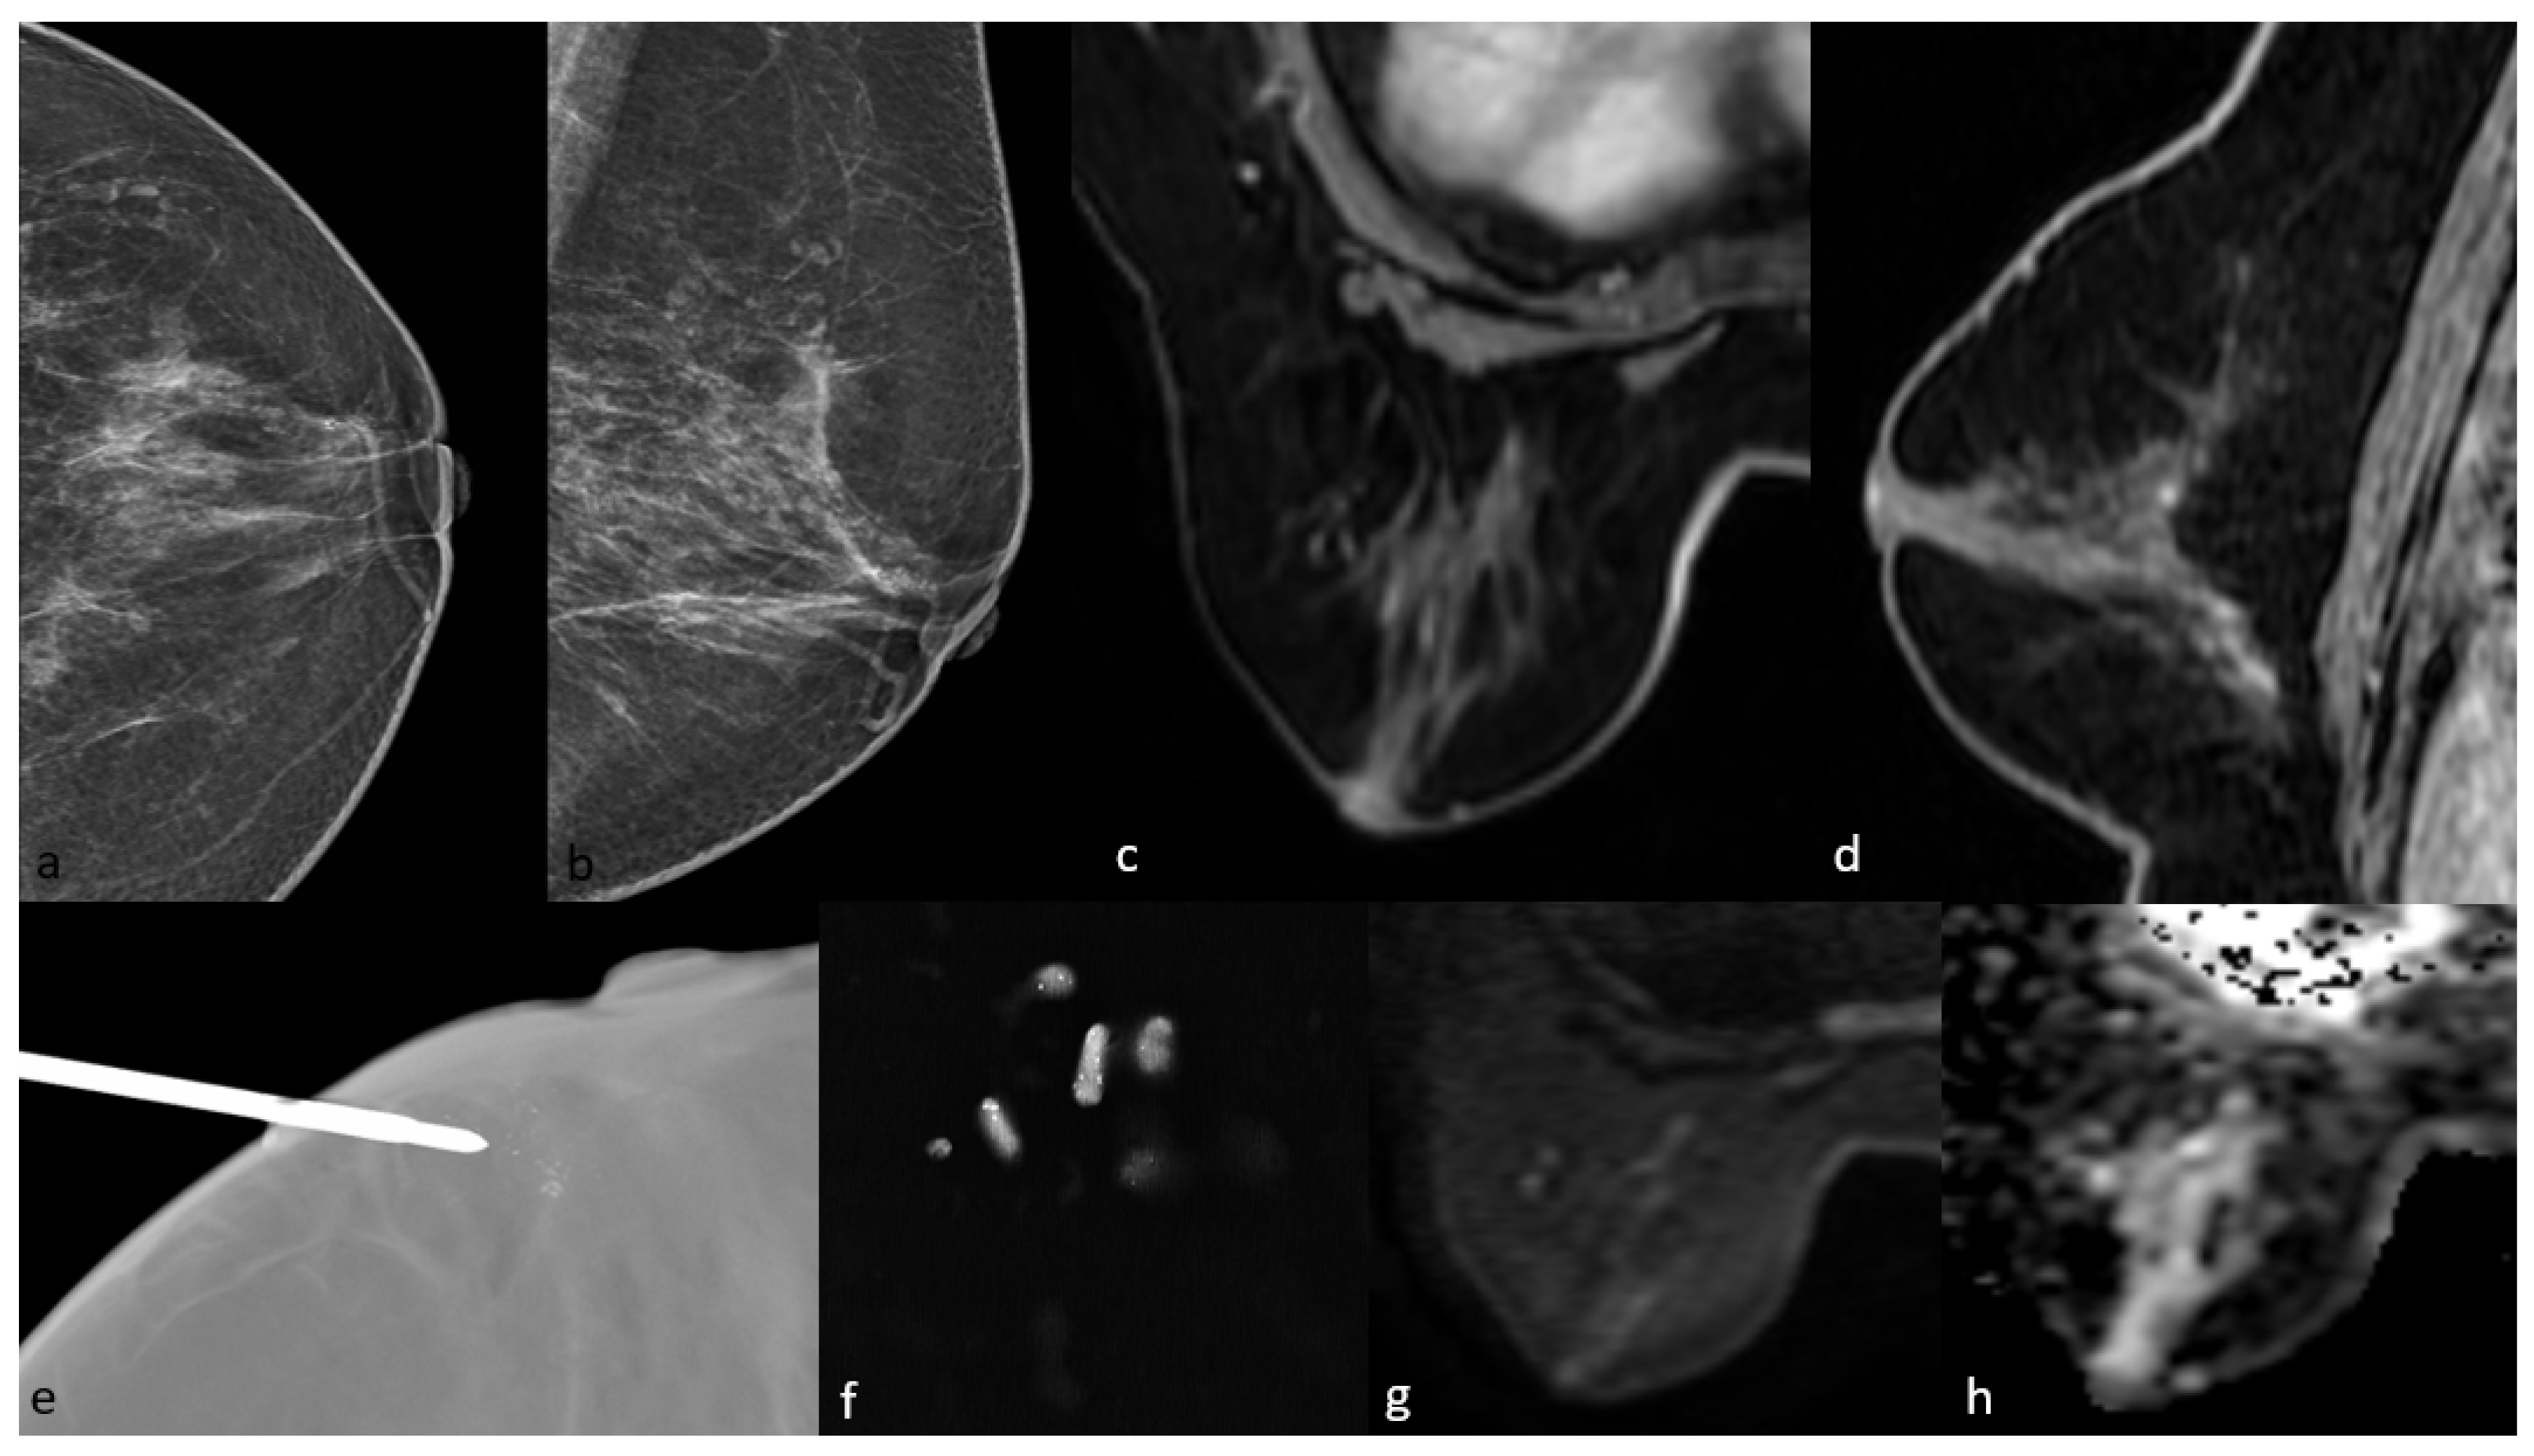

3.1. Mammographic Findings

3.2. Magnetic Resonance Imaging Findings